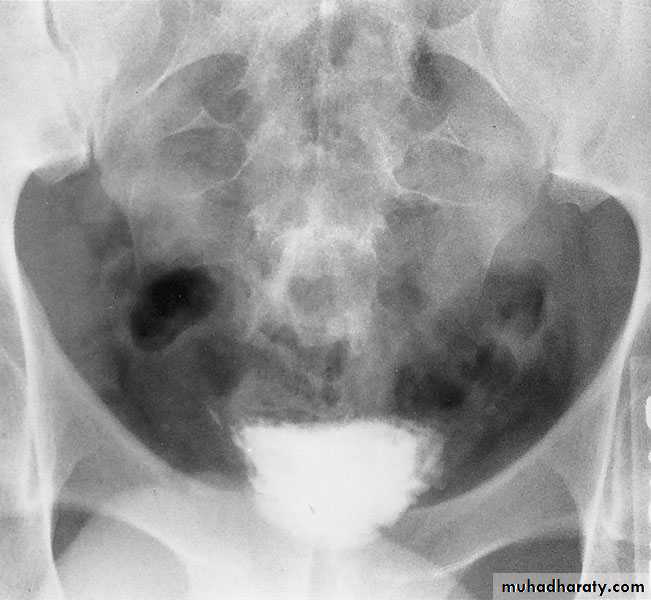

CYSTOURETHROGRAPHY

Contrast-enhanced imaging of the lower urinary tract provides valuable information on the function and anatomy of the bladder and urethraVoiding ( micturating) Cystourethrography (MCUG): looking for vesicoreteric reflux